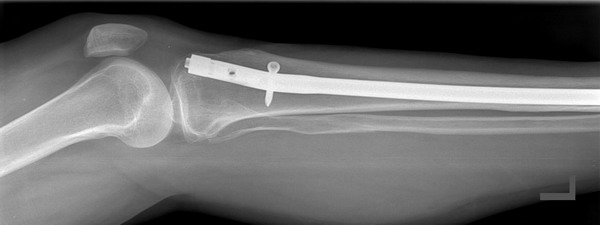

Ein gutes Beispiel für solch eine Entwicklung ist unser Universal Marknagel Extraktor. Dieses Produkt wurde zusammen mit Herrn Dr. Ferber entwickelt.